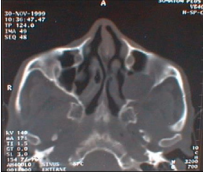

Figure 4 CT axial plane: left maxillary sinus mucocele (lysis of post sinus wall).

Figure 4: CT axial plane: left maxillary sinus mucocele (lysis of post sinus wall).

Symptomatology is not specific. We can found nasal obstruction, rhinorrhea, epistaxis, facial pain, facial deformation, proptosis, peri orbital swelling, epiphora, palatal deformity, dental problems or radiologic discovery. Nasal endoscopy shows anomalies of lateral nasal way (disformed). Computed tomography in the axial and coronal plane gives a reliable extension balance, the sinus is enlarged with wall blowed reduced or interrupted. Its contents isodense or hypodense and no contrast enhancement, unless infected.